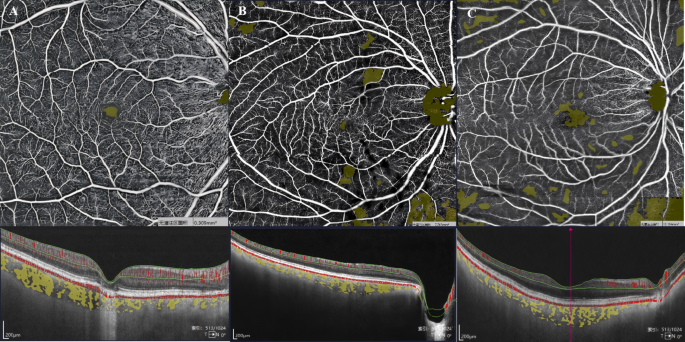

To minimize segmentation-related bias, particularly in eyes with markedly thin retinas, OCTA metrics were cross-checked against the corresponding B-scan images after automated slab generation. Using the retinal SVC as an example, we illustrate macular microcirculation. Figure 4 presents SVD images from three subjects: Fig. 4A, a 63-year-old healthy female with no visual-field defect; Fig. 4B, a 59-year-old female with CPACG and a visual-field MD of −10.45 dB; and Fig. 4C, a 64-year-old female with CPACG and an MD of −17.62 dB. The upper row shows automatically segmented OCTA en face images, where macular microcirculation appears best in Fig. 4A, intermediate in Fig. 4B, and poorest in Fig. 4C. For comparison, the lower row shows images based on manual slab delineation guided by structural OCT B-scans, confirming the same pattern: vessel density is highest in Fig. 4A and lowest in Fig. 4C.

Representative images illustrating macular retinal SVD in three subjects: one healthy control and two CPACG patients with different disease severities. The upper panels show OCTA images, where yellow areas indicate non-perfusion regions. The lower panels show the corresponding OCT B-scans, with the retinal SVC defined as the area between the two green segmentation lines. (A) A 63-year-old healthy female without visual field defects, showing a dense capillary network with minimal non-perfusion areas and high vascular density. (B) A 59-year-old female with CPACG (mean deviation = − 10.45 dB), showing a moderately dense capillary network, medium-sized non-perfusion areas, and moderate vascular density. (C) A 64-year-old female with CPACG (mean deviation = − 17.62 dB), showing a sparse capillary network, extensive non-perfusion areas, and reduced vascular density.